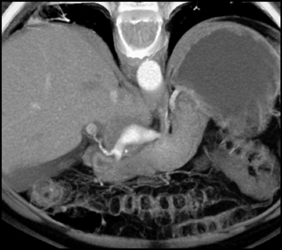

CASE NUMBER 2,014

Hepatic Artery Aneurysm